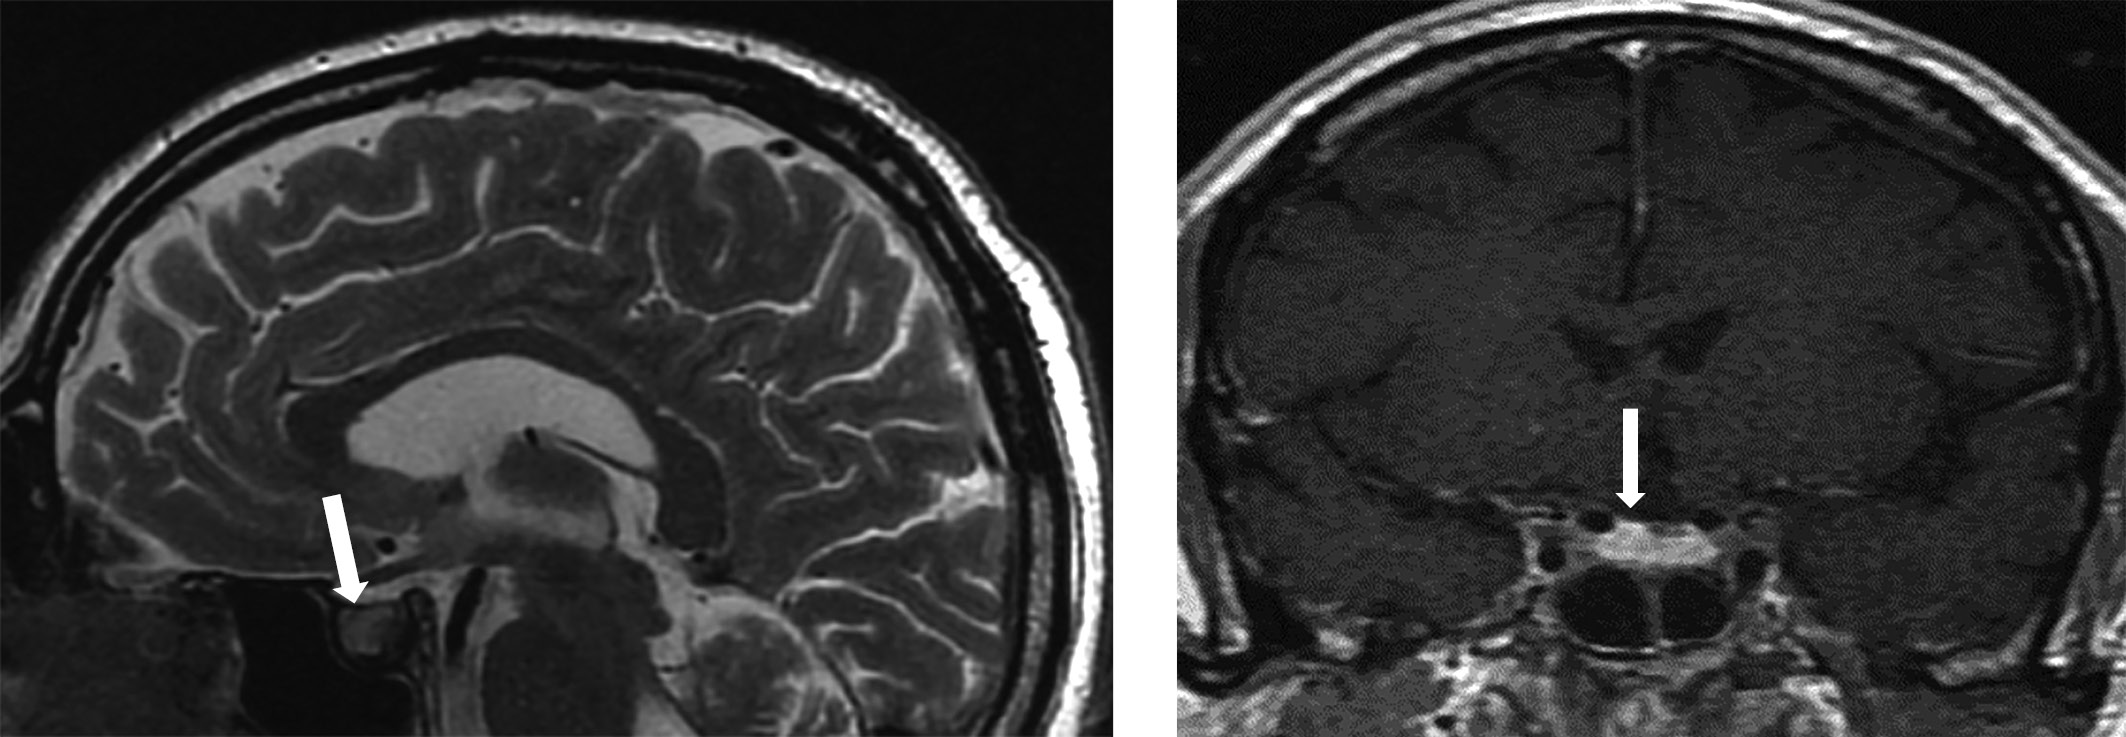

По результатам МРТ головного мозга отмечалась положительная динамика в отношении воспалительного процесса в гипофизе: деформация и выраженная неоднородность структуры гипофиза, нарушение функций нейрогипофиза, соответствующие гипофизиту, по сравнению с предыдущим исследованием — уменьшение вертикального размера гипофиза.

МРТ-исследование не выявило опухолевых образований, однако визуализированный гипофиз деформирован, его размеры составили по вертикальному сечению — 8 мм, поперечному — 16 мм, переднезаднему — 15 мм (рис. 1). Тогда как размеры гипофиза при предыдущем исследовании были больше — 13×22×16 мм соответственно (рис. 2). Структура аденогипофиза неоднородна, в том числе за счет формирования фиброзных изменений в задней части, а при контрастном усилении отмечается выраженное неоднородное накопление контрастного вещества с наличием гиповаскулярных участков, соответствующих фиброзным изменениям. Выявлено активное накопление парамагнетика прилегающей твердой мозговой оболочкой, что соответствует синдрому «дурального хвоста». Воронка не утолщена, расположена срединно. Задняя доля гипофиза достоверно не визуализировалась.

Рисунок 2. МР-картина хиазмально-селлярной области.

Сагиттальный и фронтальный срезы.